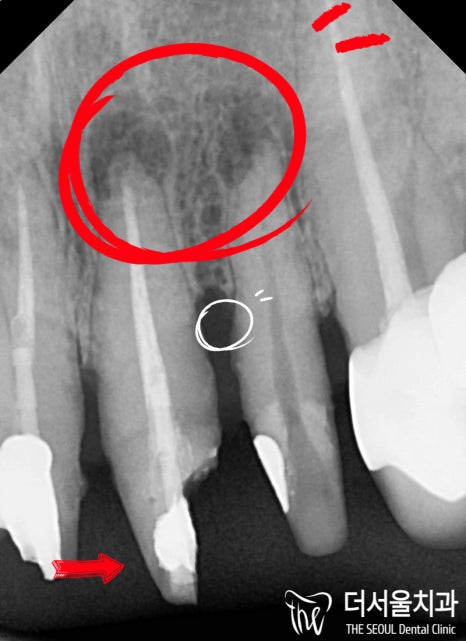

파노라마(X-Ray) 촬영 결과,

뿌리 깊숙히 세균이 침투하여

썩게 만들었는데요.

단순히 치아 신경치료로 해결될 것이

아닌 사례였었습니다.

곳곳에 깨진 것도 있었으며,

뿌리 끝에는 염증까지 나타날 정도로

이가 썩었었기에

얼른 문제를 해결해드려야 되었습니다.

#22 앞니 부러짐 쪽을 확인 결과,

발치 즉시 GBR(골유도재생술)을

시행해줘야 되었습니다.

게다가 전치부 절단면 구멍 (incisal hole) 형성이 있었으며,

Undercut 때문에 더욱 꼼꼼히 심어드려야 되었죠.